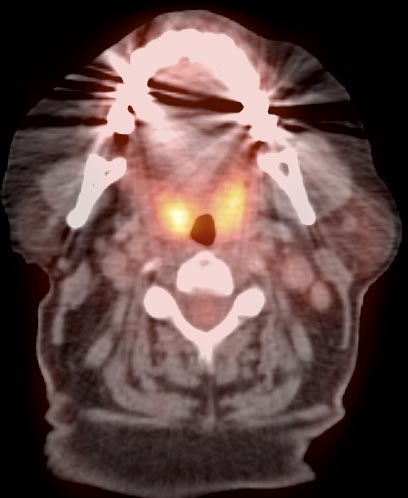

Palatine Tonsils

The palatine tonsils frequently demonstrate very intense metabolic activity.

Interpretation of tonsillar uptake is depends on the clinical presentation of the patient, the degree of FDG uptake, the size of the tonsils and the bilateral or unilateral nature of the findings.

- Bilateral and fairly symmetric FDG-uptake in non-enlarged palatine tonsils is almost always a normal finding.

- Bilateral and fairly symmetric FDG-uptake in enlarged palatine tonsils is nearly always inflammatory in nature (although can occasionally be seen with lymphoma).

- Unilateral or asymmetric increased FDG uptake within one palatine tonsil warrants careful and detailed assessment (addressed in detail, here).